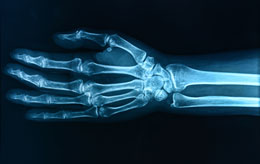

- Anxiety pain in arms

Anxiety Pain in Left Arm

The symptom of anxiety pain in the left arm has been noticed by several people when they have a

bout of anxiety. They first notice the pain in their arm and later realize that they were anxious over something. Along with that, there is also chest pain and a tingling sensation up and down their arms or fingers.